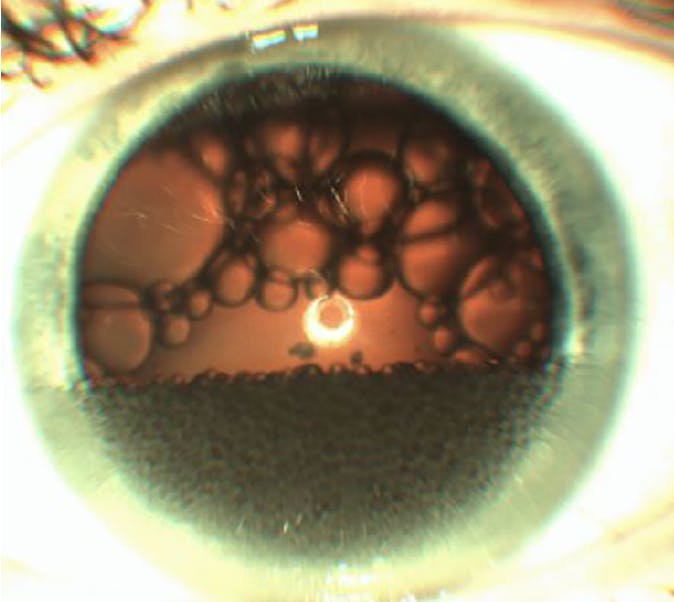

There are several causes of the particulate glaucomas, a term coined by one of us (S.C.). One common etiology is silicone oil emulsification (Figure 1). Silicone oil droplets never absorb; instead, they become embedded in the trabecular meshwork, impeding aqueous outflow, and they often become trapped in the zonules, residual peripheral vitreous, epiretinal membranes, and capsular bag.4

<p>Figure 1. Diffuse silicone oil emulsification in the anterior chamber.</p>

Figure 1. Diffuse silicone oil emulsification in the anterior chamber.